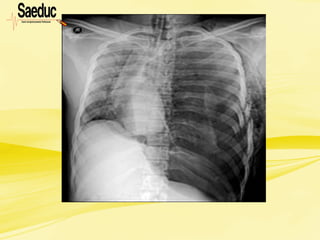

Pneumotórax hipertensivo

Quando suspeitar? na presença de:

• Extrema ansiedade, taquipnéia intensa, taquicardia,

hipotensão, cianose, dor torácica, respiração superficial;

• Sinais precoces: ruídos respiratórios ausentes ou

diminuídos do lado afetado, aumento progressivo da

dispnéia e taquipnéia, apesar do tratamento, percussão

timpânica;

• Sinais tardios: ingurgitamento da veia jugular, desvio da

traquéia, sinais de hipóxia aguda, timpanismo à

percussão do tórax, pressão de pulso diminuída,

hipotensão, sinais de choque descompensado.